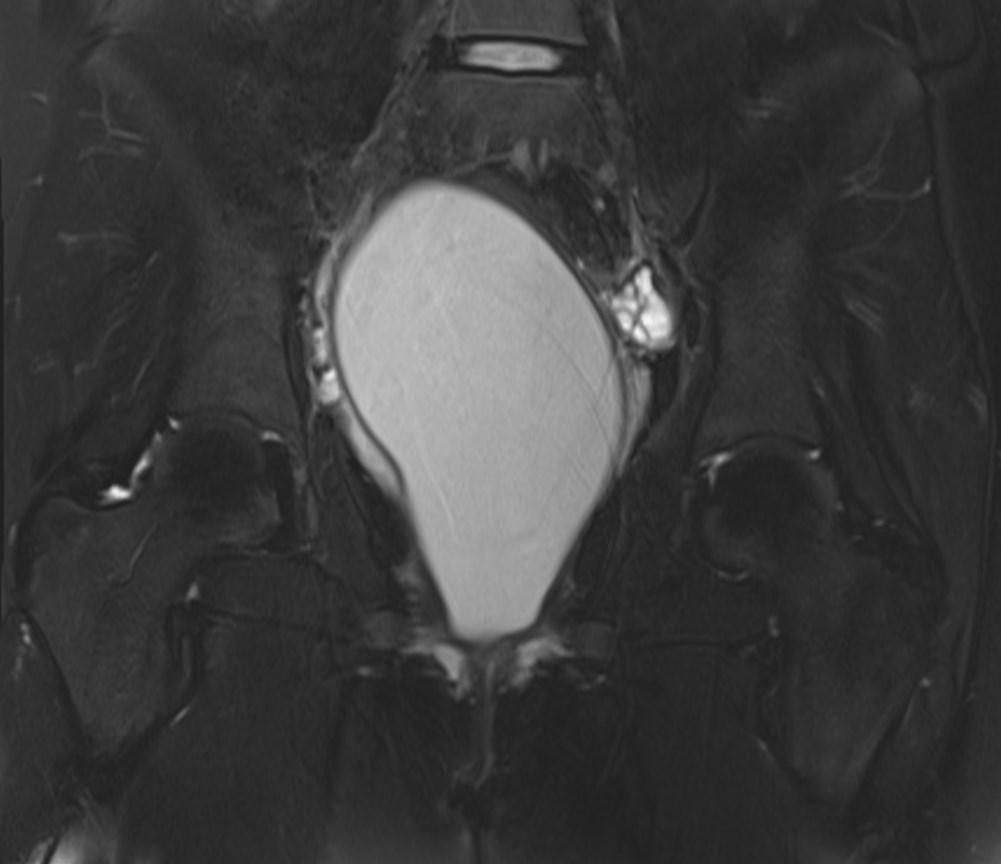

MR images showed hemorrhagic fluid in a distended vagina. The uterine cavity is not dilated.

In haematocolpos, there is accumulation of menstrual blood in the vagina in the setting of an anatomical obstruction, usually an imperforate hymen. When there is concurrent uterine distention, the term haematometrocolpos is used.